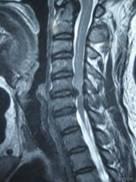

7、脊髓型颈椎病

(1)发病率10%~15%

(2)病因:慢性椎间盘退变,突出、椎体后缘骨赘、后纵韧带钙化、黄韧带肥厚

(3)脊髓型颈椎病的治疗

a.下肢肌张力不同程度的增高和肌力减损

b.快走易跌倒、步态蹒跚

c.手笨拙,无力

d.外科手术治疗